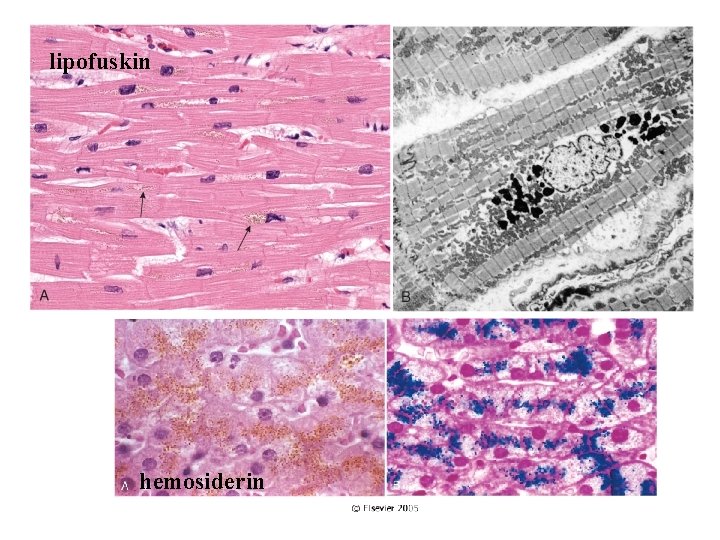

3. Enzim eksikliği sonucu endojen materyal birikir Lizozomal depo hastalığı 4. Anormal bir eksojen veya endojen madde birikimi (Pigment birikimi) – Dışardan gelen metabolize edilemeyen veya atılmayan maddeler (karbon partikülleri, silika tozları) – Metabolize edilemeyen endojen pigment birikimi: Lipofuskin, Demir, Melanin • Birikim reversibl olabilir. • Depo hastalıklarında birikim ilerleyicidir. Sekonder zedelenme ile hücre ölümüne yol açabilir.

lipofuskin hemosiderin